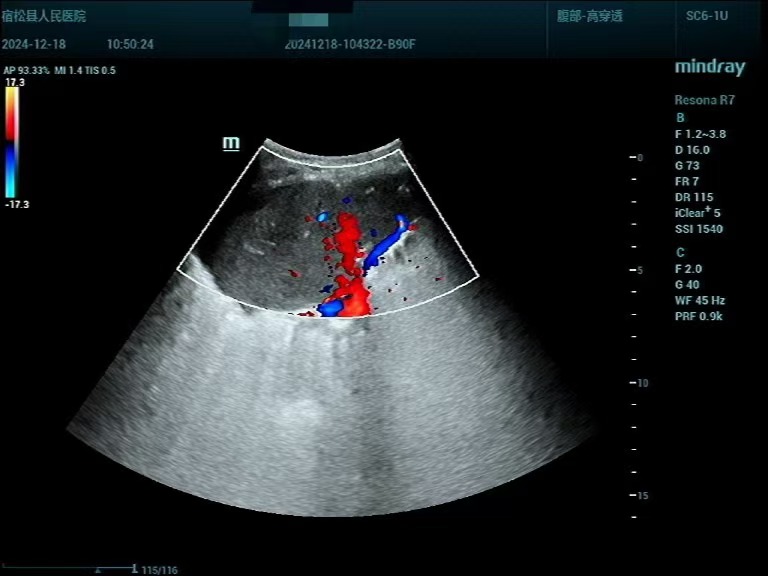

患者男性,83岁,发现肺部占位入院。其胸部CT提示右肺上叶肿块,纤支镜未能取到病理结果、建议进一步检查,呼吸内科评估后考虑肿块为恶性肿瘤的可能性大,需要进一步行活检以明确病理诊断。在征求家属意见后,超声诊断中心为其进行超声造影联合超声定位下肺肿块穿刺活检,该患者肺部病灶位于右肺上叶,结合不同频率超声探头检查,清晰显示了病灶内部结构及血流灌注情况。造影结束后,初步判断该肿物为恶性肿瘤的造影模式,在超声引导下,避开病灶大血管及坏死区,穿刺针取出肺部病变适量标本,活检病理结果提示鳞状细胞癌,为该患者的下一步诊治提供了充分依据。

▲常规超声表现:右肺上叶肿块